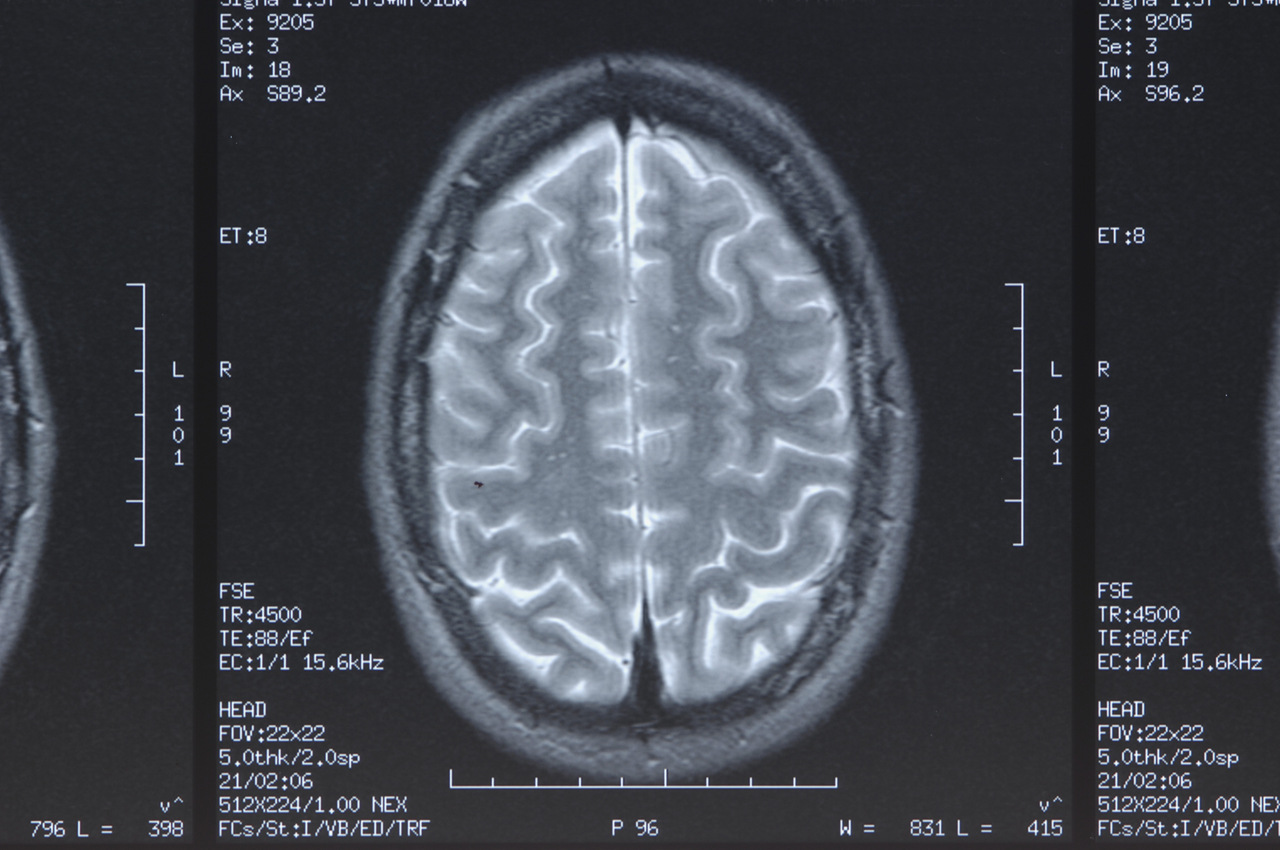

دماغ الجنين من أعقد وأدهش ما يخلقه الله

إن تطوّر دماغ الجنين يحدث بسرعة مذهلة تفوق الخيال. حيث يبدأ تكوّنه منذ الأسبوع الثالث للحمل. في هذه المرحلة يتشكل ما يُسمّى الأنبوب العصبي، وهو الأساس الذي سيتحول لاحقاً إلى: الدماغ والحبل الشوكي، لهذا السبب يكون حمض الفوليك مهماً جداً في بداية الحمل.

ينمو دماغ الجنين عبْر مراحل دقيقة:

في الأشهر الأولى: تتكوّن الأجزاء الأساسية، وهي الدماغ الأمامي (التفكير والعاطفة لاحقاً)، الدماغ الأوسط (الحركة والحواس)، الدماغ الخلفي (التنفس والتوازن).

من الشهر الرابع فصاعداً: تبدأ الخلايا العصبية بالاتصال ببعضها، وتتشكل الشبكات العصبية الأولى. وفي الثلث الأخير من الحمل: ينمو الدماغ بسرعة هائلة، وتتضاعف الوصلات العصبية، ثم يبدأ الدماغ بتنظيم الحركات والاستجابات. والمثير للدهشة أن دماغ الجنين يعمل داخل الرحم، لكن بطريقة مختلفة عن البالغين: فهو يتحكم في التنفس التلقائي (تدريب، وليس تنفساً حقيقياً)؛ بل بضربات القلب، والحركات، يستجيب: للأصوات وللضوء، وللمس والضغط. ومن أغرب المعلومات عن دماغ الجنين، أنه يمر بمراحل تشبه مرحلة النوم الحالم (REM)؛ أيْ أنه قد يكون يحلُم داخل الرحم، رغم أن العلماء لم يكتشفوا تفاصيل هذه الحقيقة بعد. يتذكر الأصوات بعد الولادة؛ فهو يسمع صوت أمه من الأسبوع 25 تقريباً، وبعد الولادة يهدأ عند سماع صوتها، ويتعرّف إلى نغمة اللغة التي سمعها في الرحم، لهذا يبكي بعض الأطفال أقل عندما تُغنَّى لهم نفس الأغاني التي سمعوها قبل الولادة.